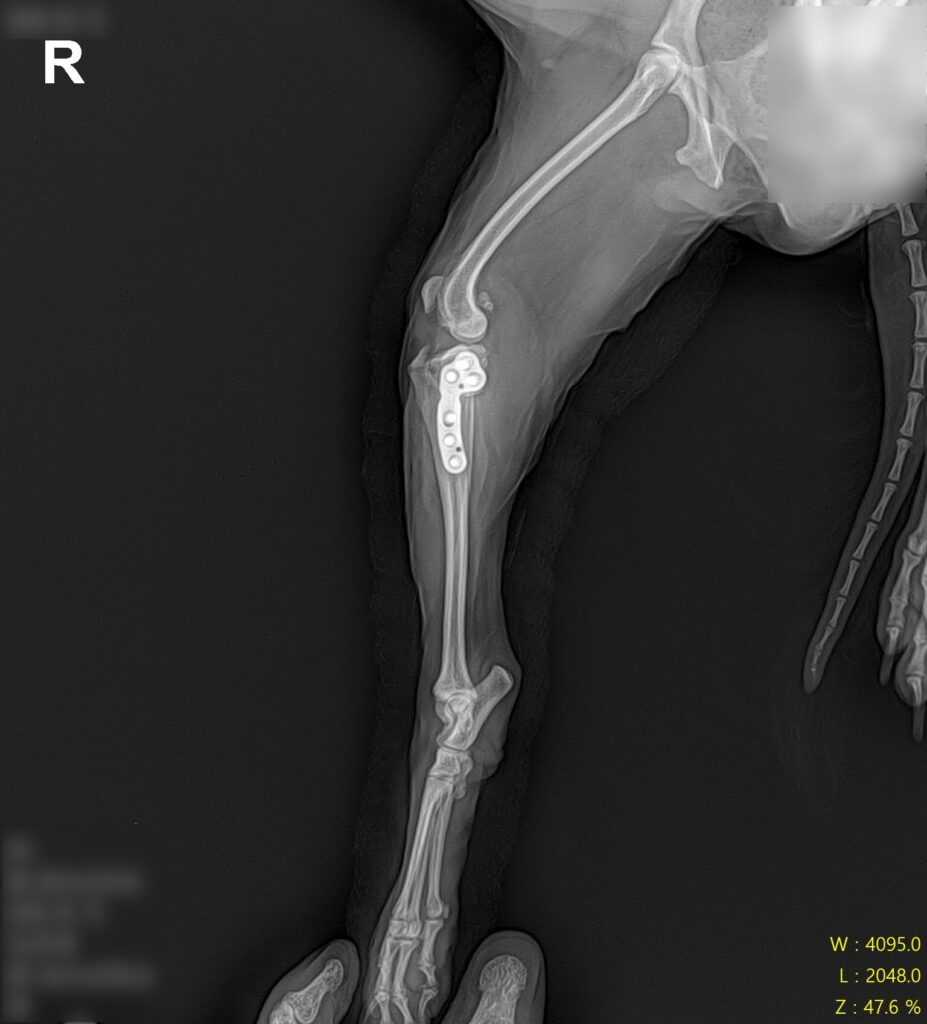

십자인대 수술 후 방사선 검사 사진 / 출처: 라온동물메디컬센터

수술 후에는 통증 관리, 체중 부하 단계 조절, 관절 가동 범위 관리, 근육 회복을 위한 재활 관리를 함께 진행하며 회복 과정을 면밀히 모니터링했습니다. 단계적인 재활 프로그램을 통해 근육을 회복시켜 나간 결과, 봄이는 정상 보행을 회복하여 퇴원하였습니다.

전방십자인대 단열로 최종 진단된 봄이에게는 TPLO(경골 고평부 수평화 골절술, Tibial Plateau Leveling Osteotomy) 수술을 진행하였습니다.

TPLO는 단순히 손상된 인대를 복원하는 방식이 아니라 무릎 관절의 역학 구조 자체를 변경하여 십자인대에 의존하지 않고도 안정적인 보행이 가능하도록 만드는 수술입니다. 소형견 고령 환자에게도 적용이 가능한 검증된 치료 방법이에요.